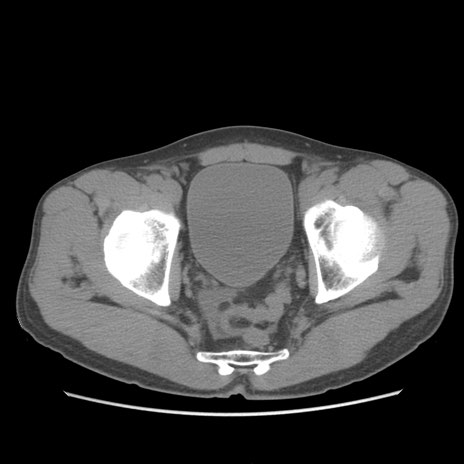

症例56 CT(横断像)

脂肪ウインドウ